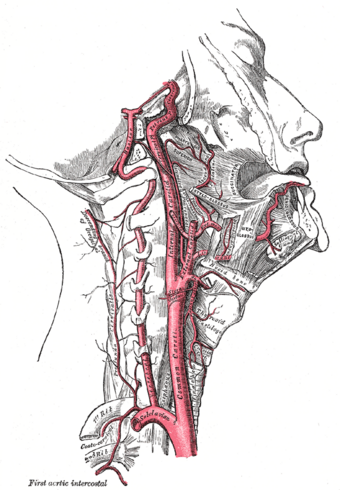

Arteries of the neck. The internal carotid arteries arise from the common carotid arteries - labeled Common caroti on the figure. | |

يُشكل الشريان السباتي والوريد الوداجي مع العصب المبهم حبلاً مشتركاً يصل عبر الرقبة إلى الرأس، ويحاط هذا الحبل بنسيجِ ضامِ يجري بين عضلات الرقبة. هذا الحبل يمر في الجزء الأسفل من الرقبة تحت العَضَلَةُ القَصِّيَّةُ التَّرْقُوِيَّةُ الخُشَّائِيّة (باللاتينية: Musculus sternocleidomastoideus)، ليصل في وسط الرقبة إلى مثلث عضلي بين العَضَلَةُ الكَتِفِيَّةُ اللَّامِيَّة (باللاتينية: Musculus omohyoideus) والعضلة القَصِّيَّةُ التَّرْقُوِيَّةُ الخُشَّائِيّة والعضلة ذات البطنين (باللاتينية: Musculus digastricus) هذا الحبل يمكن تحسسه بالإصبع من خلال تحسس نبض الشريان السباتي هناك[4].

هناك شريانان سباتيان، السباتي الأيمن والسباتي الأيسر، حيث ينبع السباتي الأيمن من الجِذْعُ العَضُدِيُّ الرَّأْسِي بينما ينبع الشريان السباتي الأيسر من الشريان الأبهر مباشرة، يسمى الشريان السباتي هنا الشريان السباتي الأصلي. السباتي الأصلي ينقسم إلى فرعين الشريان السباتي الظاهر و الشريان السباتي الغائر.

ينبع الشريان السباتي الأصلي الأيمن من الجذع العضدي الرأسي بينما ينبع الشريان السباتي الأصلي الأيسر مباشرةً من الشريان الأبهر بالإتجاه القِحْفي لينقسم - دون أن يُعطي فروعاً قبل ذلك - إلى فرعية الرئيسين الظاهر والغائر. قبيل الانقسام يتوسع ليشكل ما يسمى بالجيب السباتي (باللاتينية: Sinus caroticus). يحوي الجيب السباتي على مستقبلات الضغط إنگليزية: Baroreceptor ومجسات الضغط الجزئي للأكسجين فيما يسمى الكُبَّةُ السُّباتِيَّة (باللاتينية: Glomus caroticum)، والذين يلعبون دوراً في تنظيم ضغط الدم وتنظيم أكسدة الدم.

هو الفرع الخارجي (خارج الجمجمة) للشريان السباتي، وتنبع منه شريانات لتروية الرقبة والوجه والرأس خارج الجمجمة (عضلات وجلد وغدد ... الخ).

فروعه الرئيسية هي:

- الشِّرْيانُ الدَّرَقِيُّ العُلْوِي.

- الشِّرْيانُ اللِّسانِي.

- الشريان الوَجهي.

- الشِّرْيانُ البُلْعومِيُّ الصَّاعِد.

- شريان الفك العلوي.

- الشِّرْيانُ الصُّدْغِيُّ السَّطْحِي.

- الشريان الأُذني الخلفي.

- الشريان الأذني السطحي.

- الشِّرْيانُ الصُّدْغِيُّ الأَوسَط.

- الشِّرْيانُ الوَجْهِيُّ المُسْتَعْرِض.

ووظيفتها جميعاً تزويد الوجه وأجزاؤه والأجزاء خارج الجمجمة من الرأس، والرقبة بالدم.